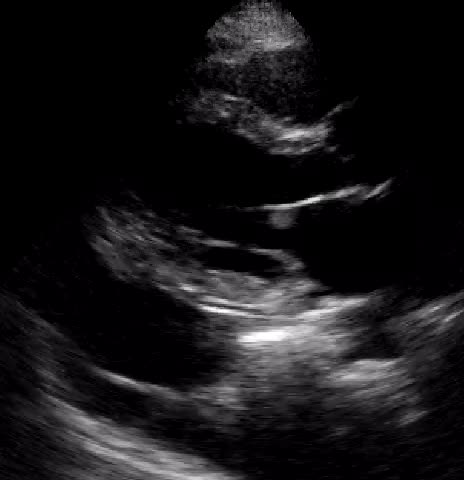

Titolo:

Endocardite su valvola tricuspide in corso di sepsi

Autore:

Laura Massironi